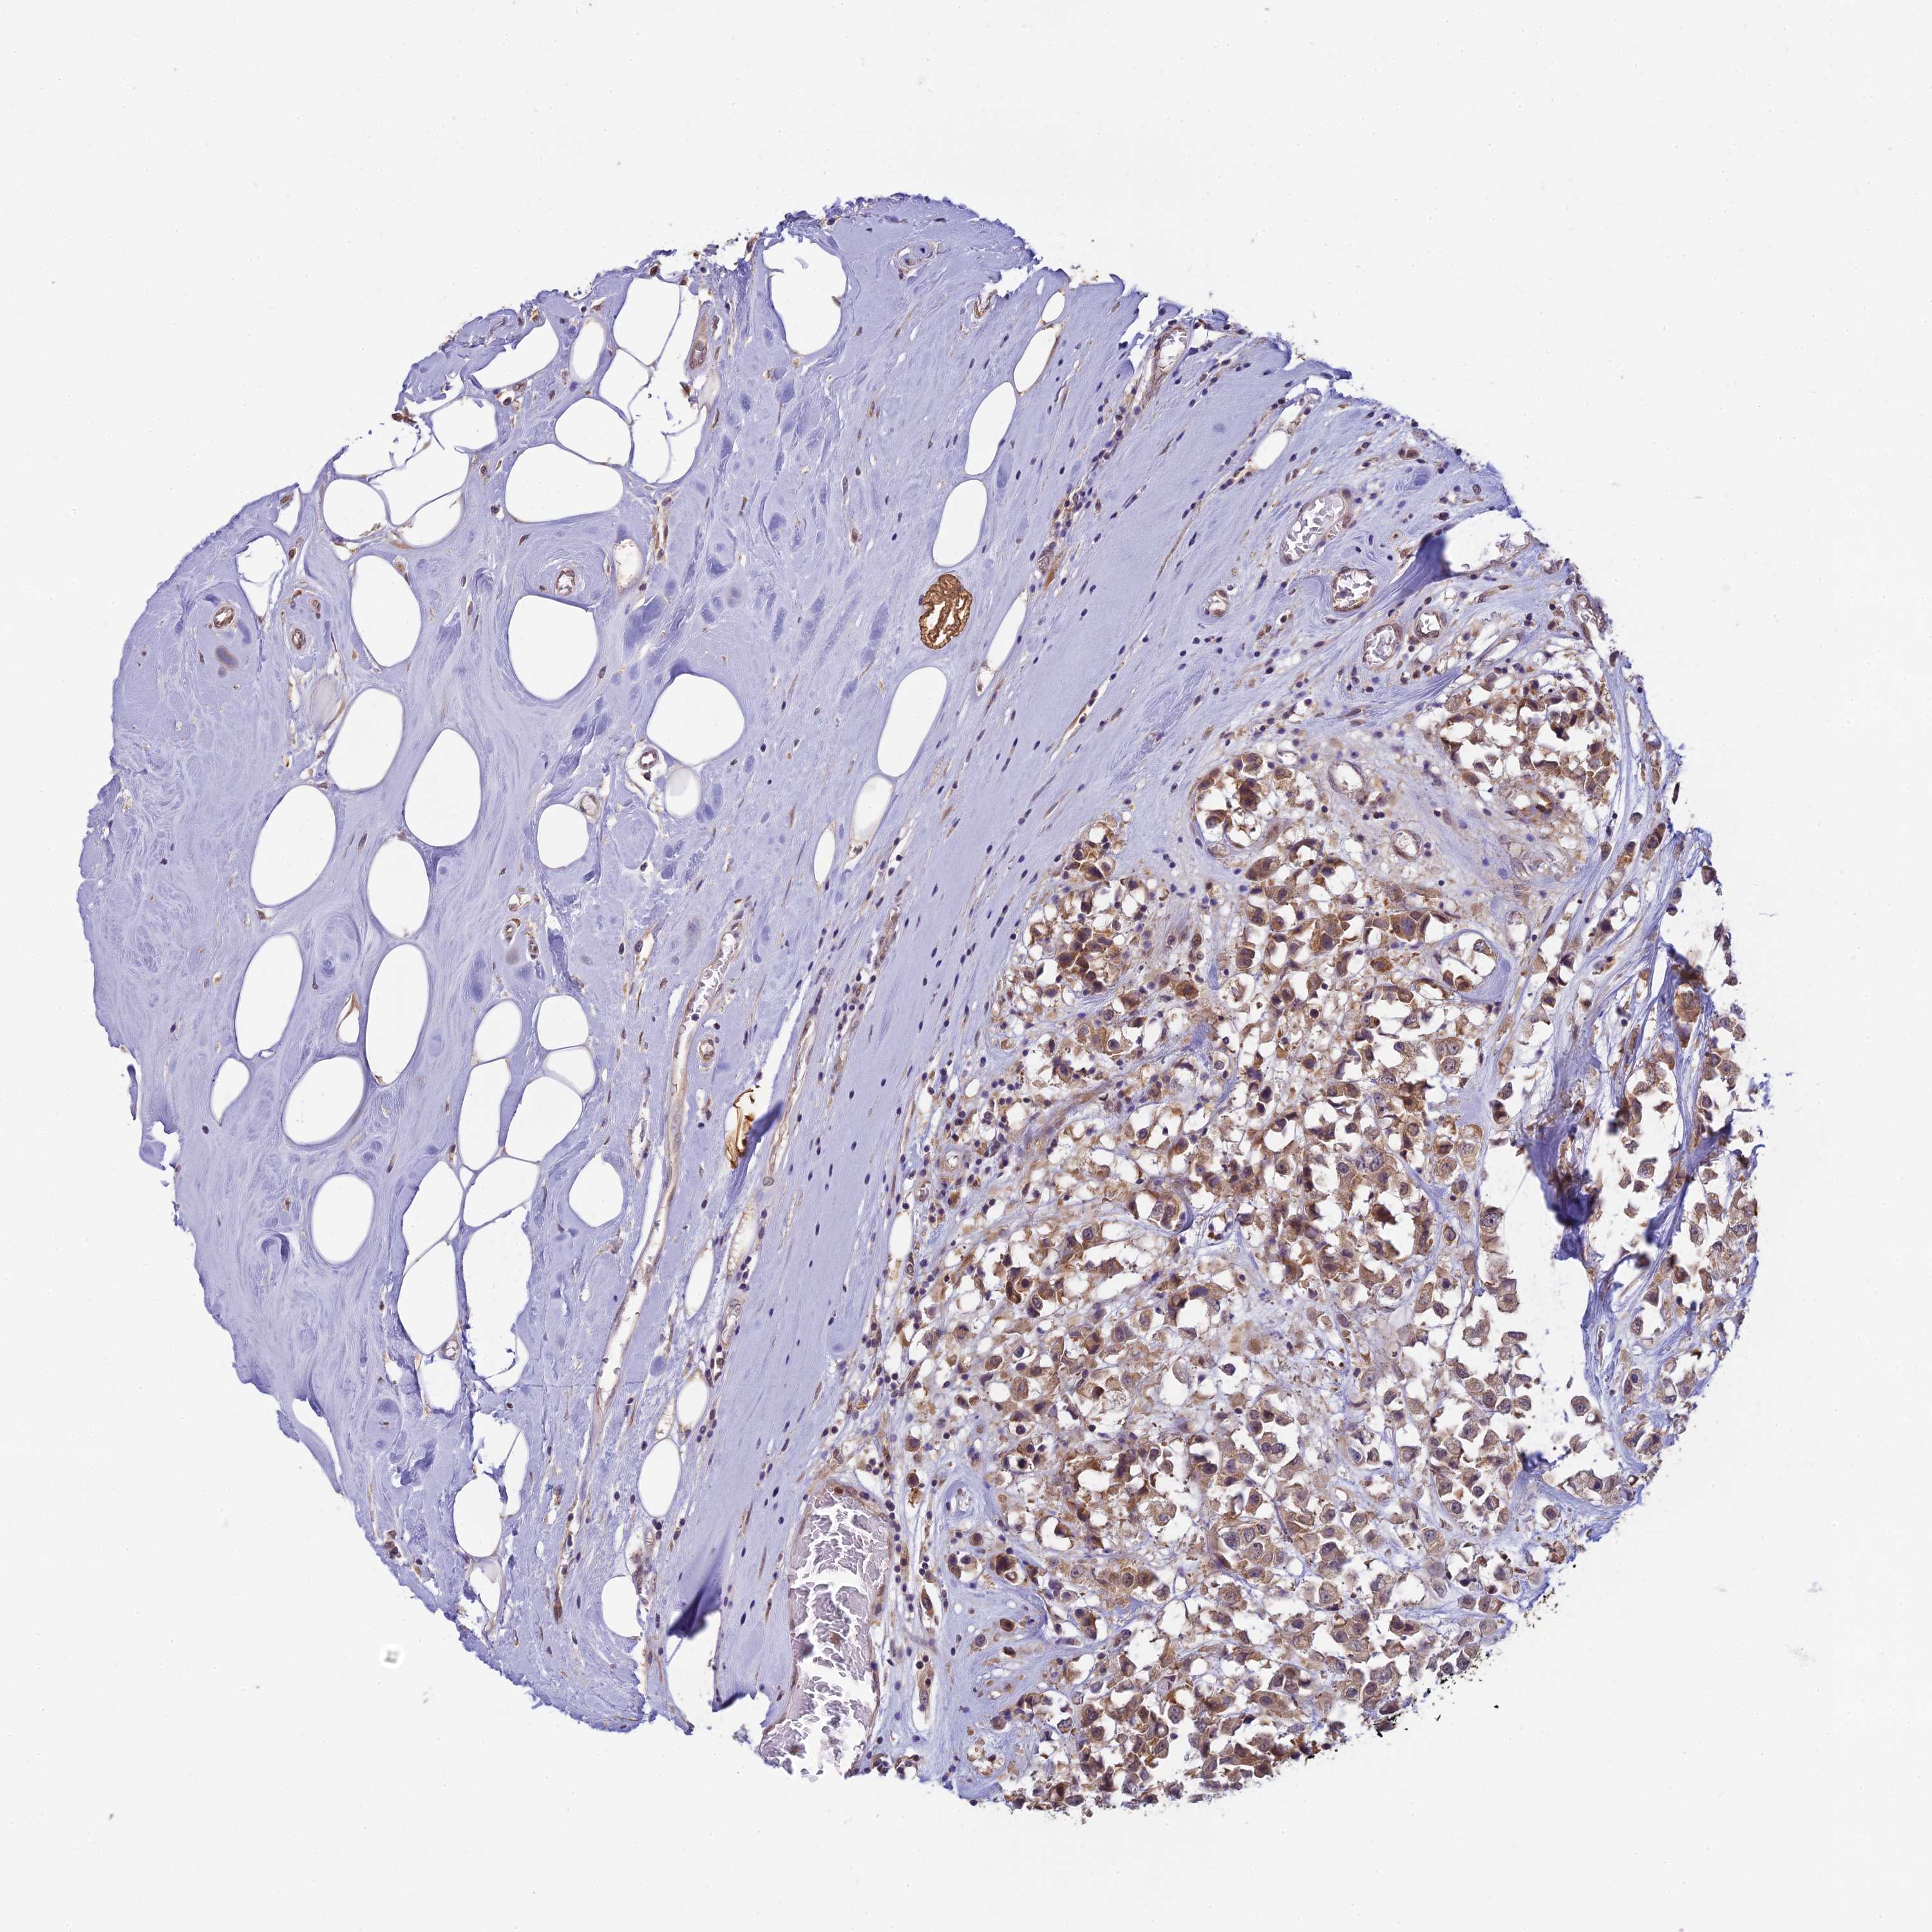

CANCER BREAST CANCER Show tissue menu

BRCA TCGA BRCA VALIDATION PROTEIN EXPRESSION